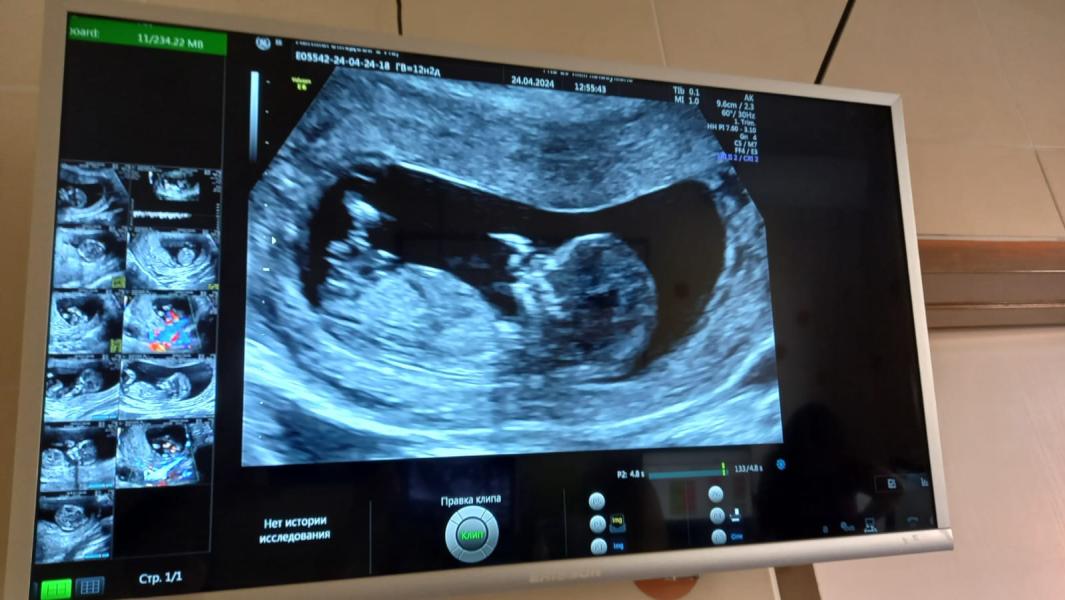

Кто там сидит?

Девочки , как думаете ,кто там сидит 🧐

Оказывается у сестры мальчик сидит в животе 😄🤓

12 недель? Мне именно с таким ракурсом не увидели пол на 16 неделе..

Да 12,